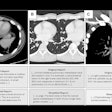

"This was a male patient in his 60s who was admitted to hospital in March 2020 with fever and shortness of breath. I was asked for my opinion on the x-ray by a respiratory physician, and as soon as I looked at it, my initial reaction was: 'Oh, wow, what am I looking at here?' It looked very unusual compared to what I would usually expect to see in a standard chest infection," he said.

Hare only recognized the image as COVID-19 because it was very similar to cases that he had been reading about in medical journals. He felt particularly proud of the interpretation of the x-ray by a radiologist because it informed the clinicians that this was a COVID-19 diagnosis -- despite the patient having a negative COVID-19 swab test. "That's very important because it shows the powerful role of imaging in determining fever in patients. Now we often get asked what a COVID lung actually looks like."

At the start of the pandemic, Hare said that his department was "seeing case, after case, after case." He described how, ordinarily, he might see one or two chest x-rays showing pneumonia in his daily workload. During the surge of the pandemic, he saw 40 to 50 cases of COVID-19 on x-rays and CT, making it a very difficult time, he noted.